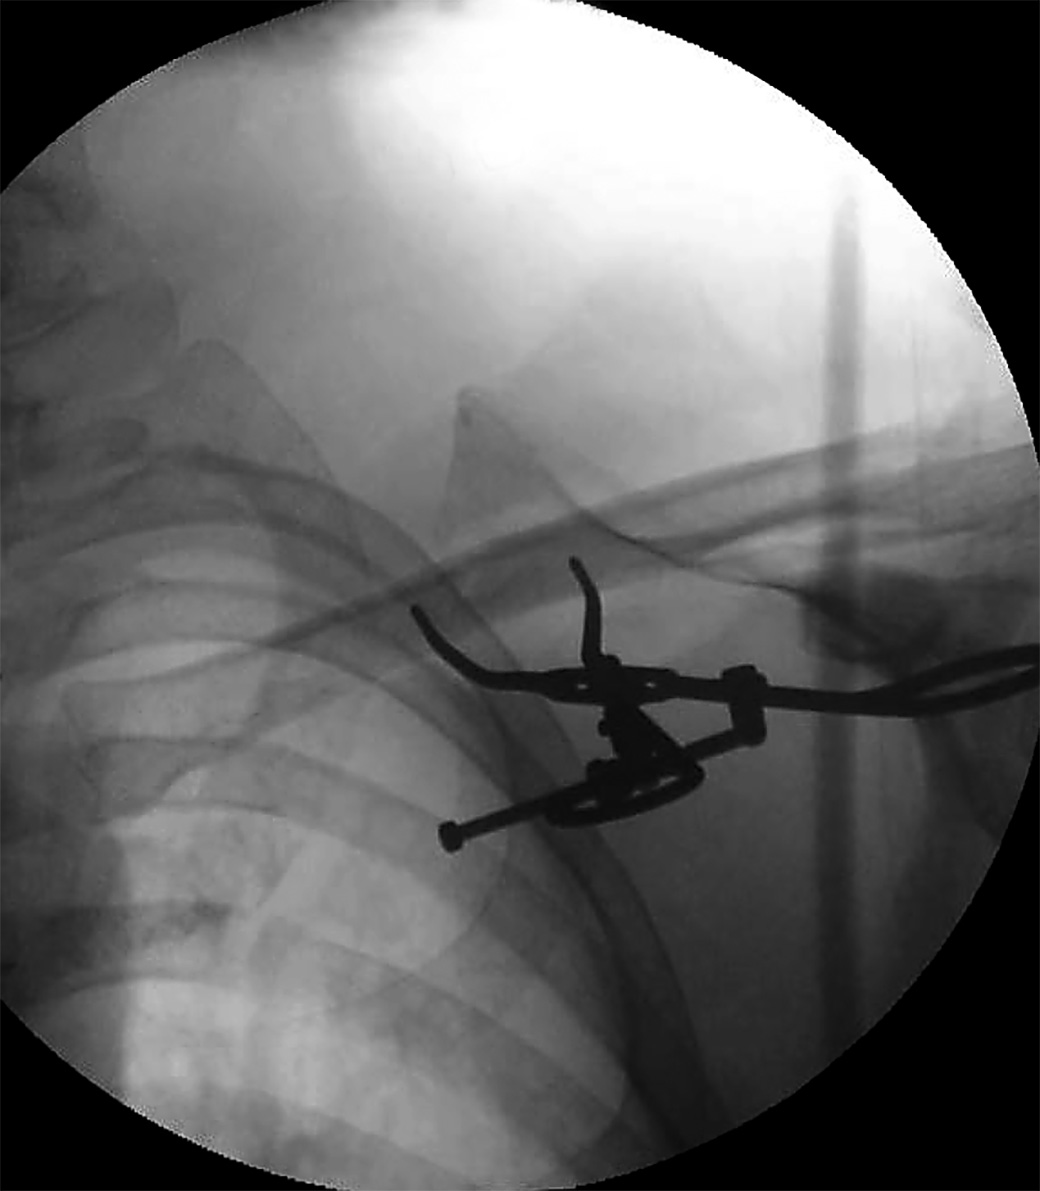

Versatile set of fracture reduction clamps, each with a specific tine design that allows for appropriate vector placement so that anatomic reduction can be obtained in a number of different types of fractures

• Clamps incorporate a box joint design that prevents clamp joint loosening and the need for tightening.

• Speed Lock Style: Extra-long spin down allows for increased range of clamp use, and open-topped joint rotates to allow for increased range of opening, and also allows for quick release